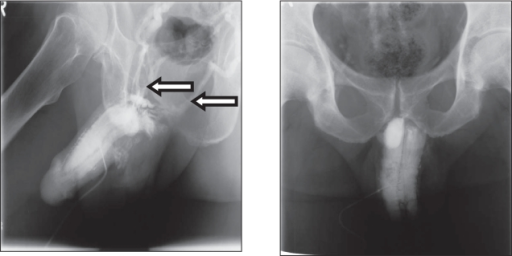

- يبدأ دكتور أحمد فودة بإجراء مجموعة مختلفة من الفحوصات التصويرية والتحاليل المخبرية لقياس مستوى هرمون التستوستيرون والبرولاكتين في الجسم مع إجراء أشعة الدوبلر على القضيب بعد حقن مواد تحفز من تدفق الدم خلال العضو الذكري وعبر الأشعة ليتم تحديد ما إذا كان هذا المريض يعاني من مشكلة التسرب الوريدي أم لا؟